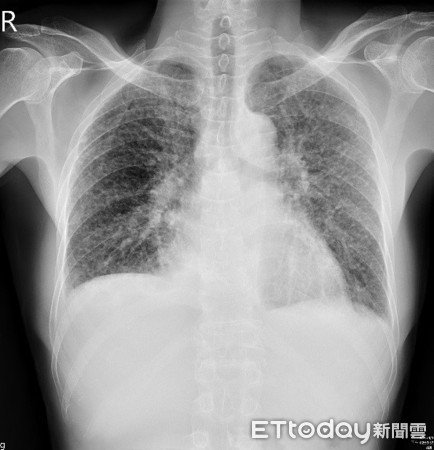

▲X光影像中,雙側肺部出現許多小白點。(圖/亞大醫院提供)

亞洲大學附屬醫院胸腔內科主治醫師林育生表示,陳先生在急診時接受胸部X光檢查,發現雙側肺部有諸多細小白點,同時也有肺部積水情形,懷疑可能為惡性腫瘤肺部轉移,或是粟粒性肺結核所致,詢問其職業暴露史和抽菸史,發現患者在建築工地上班,且菸齡超過20年,轉介至胸腔外科進行肺部手術切片,證實為「矽肺症」惹的禍。

林育生建議,一般塵肺症患者的肺部X光片會看到雙側肺葉多發性的白點,一開始常被當成粟粒性肺結核,或轉移性肺腫瘤,且患者到晚期會因漸進性大範圍的肺纖維化,甚至被誤認為肺腫瘤,臨床診斷大部分需依靠明確的暴露史與影像檢查,以排除其他可能,有時甚至需要外科手術病理切片方能確診。